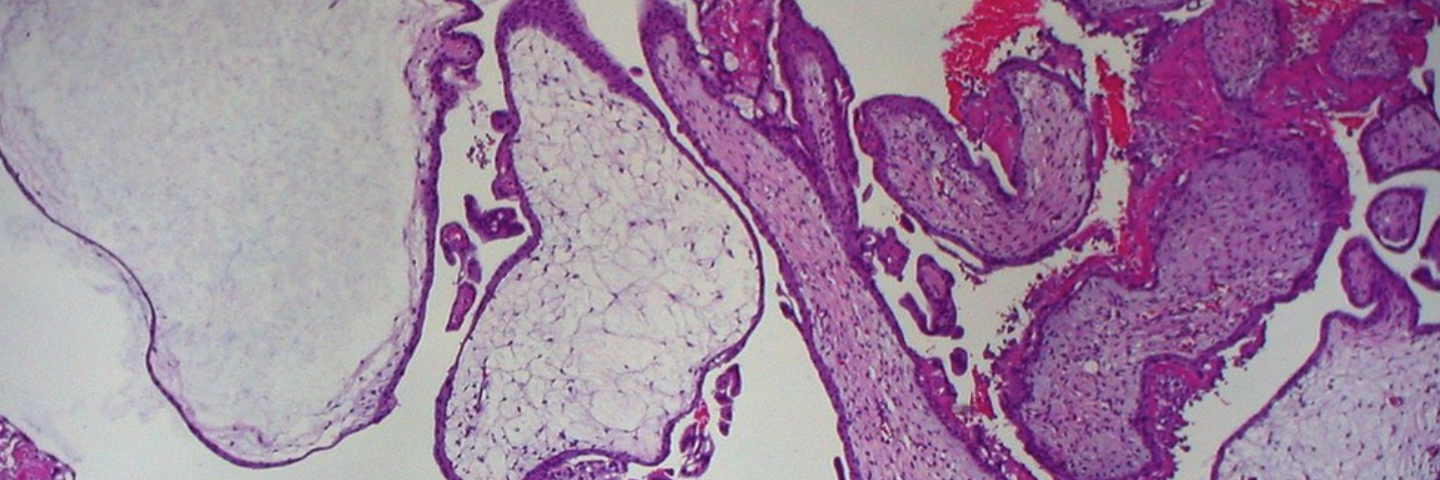

Welcome to the Miami Project Human Spinal Cord Collection